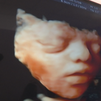

¿Cómo no sentiríamos si viésemos por primera vez al amor de nuestra vida? La ciencia y la tecnología avanzan y no dejan regalos como las ecografías 5D. Después de una larga espera, a pocas semanas para nacer, las mamás de Hugo y Pablo les han podido poner cara.

Ecografías en 5D, la imagen más realista que se puede obtener del bebé antes del parto